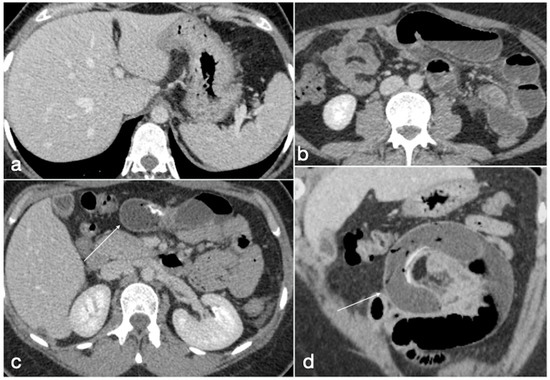

Figure 22. Patient 4. Leak from excluded stomach after gastric bypass. A 47-year-old male patient with previous gastric bypass was complaining of abdominal pain and fever. Note the surgical sutures of the gastric bypass (a,b, axial view) and in (c) the fluid collection (circle) that seems to arise from the excluded stomach (d, circle) and not supplied after the oral contrast administration (e,f axial views). According to the interventional radiologist and the surgeon, it was decided to conservatively treat the patients and at the CT follow-up 13 days later the fluid collection was reduced (g, axial view; h, coronal view, arrows).